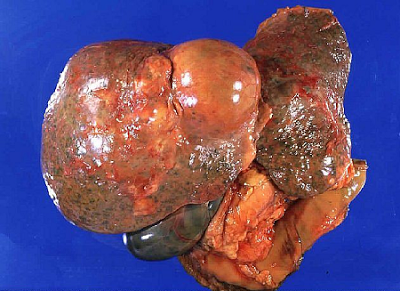

Υπάρχουν δύο διαφορετικοί τύποι καρκίνου του ήπατος. Ο πρωτοπαθής που αρχίζει από το ήπαρ, και ο δευτεροπαθής που εμφανίζεται σε άλλο μέρος του σώματος και εξαπλώνεται (κάνει μετάσταση) και στο ήπαρ. Είτε είναι πρωτοπαθής, είτε μεταστατικός, έχει συνήθως πολύ κακή πρόγνωση.

Όταν ο αρχικός κακοήθης όγκος αναπτύσσεται σε κάποιο μέρος του ήπατος, ονομάζεται ηπατοκυτταρικό καρκίνωμα ή κακόηθες ηπάτωμα ή πρωτοπαθής καρκίνος του ήπατος και αν ο όγκος στο ήπαρ προέρχεται από μεταστάσεις καρκίνου από άλλα όργανα, όπως από το παχύ έντερο, στομάχι κλπ., ονομάζεται μεταστατικός καρκίνος του ήπατος. Στα παιδιά παρουσιάζεται ένας άλλος τύπος καρκίνου του ήπατος, το ηπατοβλάστωμα.

Ο μεταστατικός καρκίνος του ήπατος είναι ο περισσότερο συχνός. Πρωτοπαθείς εστίες μπορεί να είναι τα έντερα, το στομάχι, ο μαστός, το πάγκρεας και οι πνεύμονες.

Από όλα τα μεταστατικά καρκινώματα του ήπατος, εκείνο που ενδιαφέρει περισσότερο είναι αυτό εκ του παχέος εντέρου για πολλούς λόγους, ειδικά δε λόγω της πιθανότητας θεραπείας και ακόμα και ίασης μετά από ηπατεκτομή.